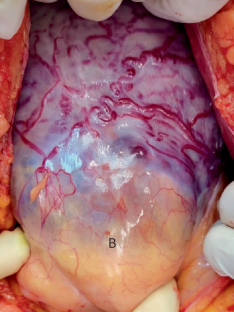

Jauniaux, E., Hussein, A. M., Elbarmelgy, R. M., Elbarmelgy, R. A. & Burton, G. J. Failure of placental detachment in accreta placentation is associated with excessive fibrinoid deposition at the utero-placental interface. Am. J. Obstet. Gynecol. 226, 243.e1–243.e10 (2022). Prospective histopathologic study showing that the abnormal attachment of placental tissue is associated with excessive fibrinoid deposition between the tip of the villi and the scarred myometrium.

Jauniaux, E. et al. A new methodologic approach for clinico-pathologic correlations in invasive placenta previa accreta. Am. J. Obstet. Gynecol. 222, 379.e1–379.e11 (2020).